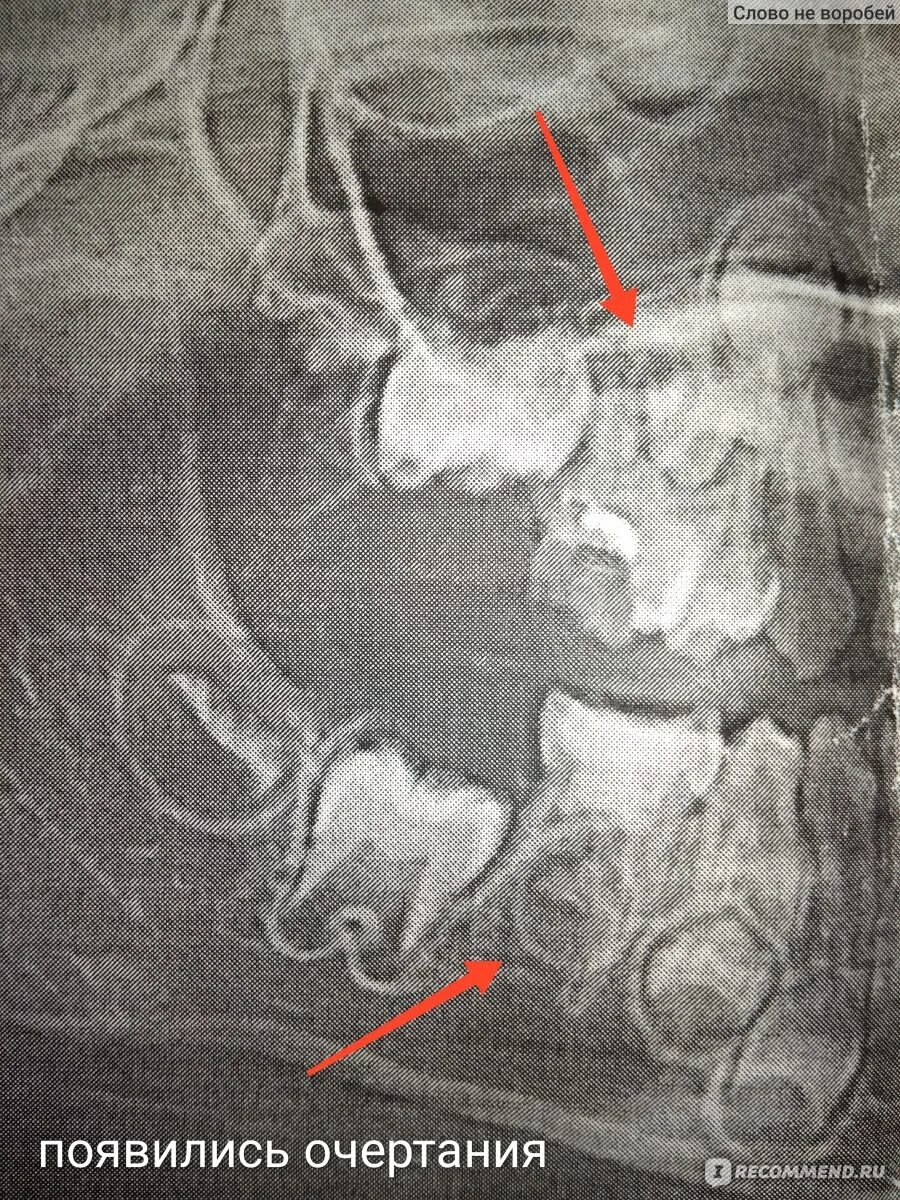

У ребенка нет зачатка постоянного зуба